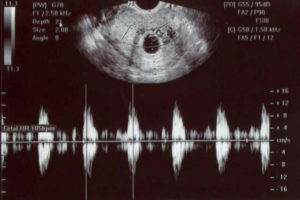

- КТГ. Кардиотокография является наиболее информативным методом получения данных о ЧСС малыша. При помощи этого аппарата на маленьких сроках выявляются такие патологии как гипоксия, свидетельствующее о нарушении в протекании беременности. Это позволяет принять экстренные меры по устранению фактора, ставшего причиной гипоксии малыша. Время процедуры составляет около часа, в течение которых беременная женщина должна лежать неподвижно. Врачи успевают оценить фазы активности и сна ребенка и сделать медицинское заключение.

Сердцебиение плода прослушивается на ранних сроках беременности на УЗИ диагностике.

При помощи данного метода исследования уже на сроке 5 недель видно плодное яйцо, имеющее размеры около 7 мм, и слышно сердечные сокращения, которые составляют примерно 100 ударов за минуту.

Для более информативного обследования на ранних сроках беременности требуется хорошая аппаратура, которая способна считывать даже самые небольшие изменения.